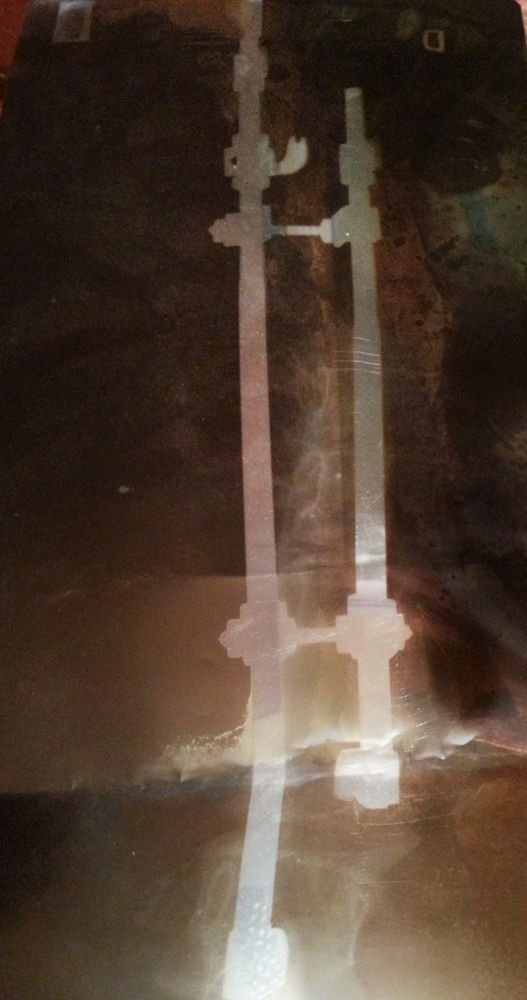

Какви са основните характеристики на сколиозата?

Каква е разликата между функционалната и структурната сколиоза?

Какви са потенциалните източници на болка при сколиоза?

Какви са основните характеристики на сколиозата?

Каква е разликата между функционалната и структурната сколиоза?

Какви са потенциалните източници на болка при сколиоза?

Как може да се коригира сколиозата без хирургическа намеса?

Какви са възможните начини за подобряване на състоянието при сколиоза?